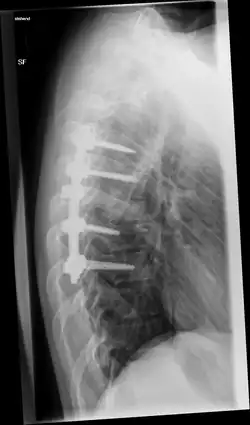

Seitliche Röntgenaufnahme einer Osteosynthese vom Brustwirbelkörper(BWK) 5/6 zu 8/9 mit Impaktfraktur und Kompression BWK 7 und Fraktur BWK 8 nach 12 Wochen

Ein zunehmendes Problem stellen osteoporotische Knochenbrüche dar. Hier ist aufgrund der Knochendichteminderung der Halt der Implantate deutlich geschwächt. Bei diesen Brüchen ist ein Prinzip zur Erhöhung der Stabilität einer Platten- oder Marknagelosteosynthese die sogenannte Augmentation. Dabei wird an Stellen mit schlechter Knochenqualität (z. B. Oberarmkopf, hüftgelenksnaher Oberschenkel) spezieller Knochenzement um die Schraubenspitzen herum eingebracht, um ein Versagen der Osteosynthese durch Ausbrechen der Schrauben zu verhindern. Auch an der Wirbelsäule findet dieses Verfahren zunehmend Verwendung.